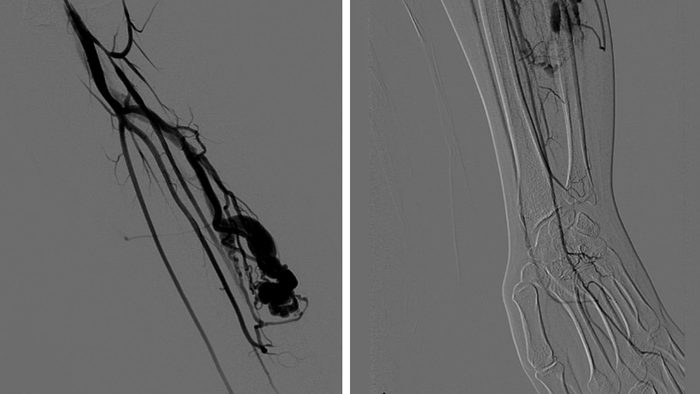

Dị dạng động tĩnh mạch cẳng tay (trái) và tình trạng thiếu máu bàn tay do hiện tượng ăn cắp máu (phải)

Kết quả thăm khám và chụp chiếu chuyên sâu bằng MRI và siêu âm Doppler mạch máu cho thấy, Q. mắc dị dạng động tĩnh mạch (AVM – Arteriovenous Malformation) nằm sâu trong cơ cẳng tay trái – một dạng bất thường mạch máu bẩm sinh tương đối hiếm gặp.

Theo TS.BS Nguyễn Ngọc Cương, Trưởng khoa Can thiệp điện quang, Trung tâm Chẩn đoán hình ảnh & Can thiệp điện quang, Bệnh viện Đại học Y Hà Nội, dị dạng động tĩnh mạch là tổn thương bẩm sinh hình thành từ khi còn trong bụng mẹ. Ở người bình thường, máu chảy từ động mạch qua mao mạch để nuôi dưỡng mô, sau đó mới trở về tĩnh mạch. Nhưng với AVM, máu đi "tắt" trực tiếp từ động mạch sang tĩnh mạch qua một đường nối bất thường.

"Dòng máu tốc độ cao bị chuyển hướng khiến các mô xung quanh không nhận đủ oxy nuôi dưỡng. Hiện tượng này trong y học gọi là steal phenomenon – tức "hiện tượng ăn cắp máu". Ổ dị dạng như một "kẻ hút máu" từ các mạch bình thường lân cận", bác sĩ Cương giải thích.